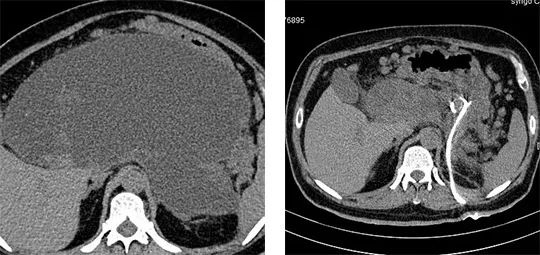

近期,我院有一位患者因腹脹主訴入院,經(jīng)我院專(zhuān)家接診查體發(fā)現(xiàn),患者上腹部膨隆明顯,看患者情況:大汗淋漓且腹脹明顯、難忍,詢(xún)問(wèn)既往病史,有重型胰腺炎病史。

開(kāi)具相關(guān)檢查,結(jié)論:胰腺假性囊腫。

立刻安排開(kāi)展微創(chuàng)治療,在CT引導(dǎo)下行經(jīng)皮胰腺囊腫外引流術(shù),5分鐘后引流成功放出咖啡色液體約400ml,查患者情況:腹脹明顯減輕,狀態(tài)良好!